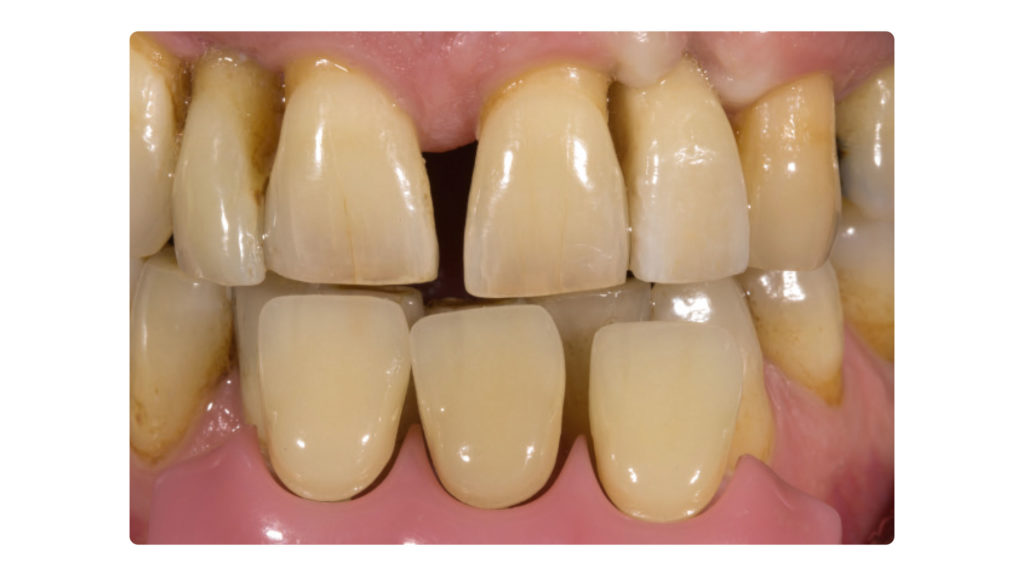

Die Implantatkrone sollte metallkeramisch gelöst werden, was wiederum bedeutete, dass für die entsprechend designte Implantatkrone ein CAD/CAM-gestützt gefertigtes Abutment (vorgefertigt, Schweden & Martina) mit einer Metallkeramik (Ceramco 3, Dentsply Sirona) verblendet werden musste. Es wurde eine zementierte Lösung gewählt, weshalb es keinen Schraubenkanal gab und somit keine Probleme mit dessen Austritt gelöst werden mussten. In den Abbildungen 6a und 6b sind die DSLR-Aufnahmen des Behandlers dargestellt. Die Referenzfarbmuster vermitteln die ungefähre Zahnfarbe, aber nicht alle Informationen und Merkmale, die für die Rekonstruktion des natürlichen Zahns vonnöten sind. Indem man die Belichtung reduziert und den Kontrast sowie die Brillanz in einem Bildbearbeitungsprogramm wie Lightroom (Adobe) erhöht, lässt sich die Histoanatomie des natürlichen Zahns besser darstellen (Abb. 6c).

Auf Wunsch des Patienten sollte der zu rekonstruierende laterale Schneidezahn die Charakteristika des mittleren Inzisiven 21, also seines direkten Nachbarzahns aufweisen. Normalerweise hätte man sich an dem noch verbliebenen lateralen Schneidezahn im ersten Quadranten orientiert, doch leider war auch dessen Zustand nicht ideal, sodass auch dieser in Bälde rekonstruiert werden sollte (Abb. 7a und b). Bei der eingehenden Betrachtung des Zahns 21 stellten wir zwar eine gewisse Ähnlichkeit mit den vom Zahnarzt gewählten Farbmusterzähnen fest, erkannten aber auch relevante Unterschiede. Aus diesem Grund starteten wir die laborseitige Analyse mit polarisierten Aufnahmen (Abb. 8a und b). Da der Patient 49 Jahre alt war, suchten wir gezielt nach charakteristischen Merkmalen natürlicher älterer Zähne und und wurden auch fündig.